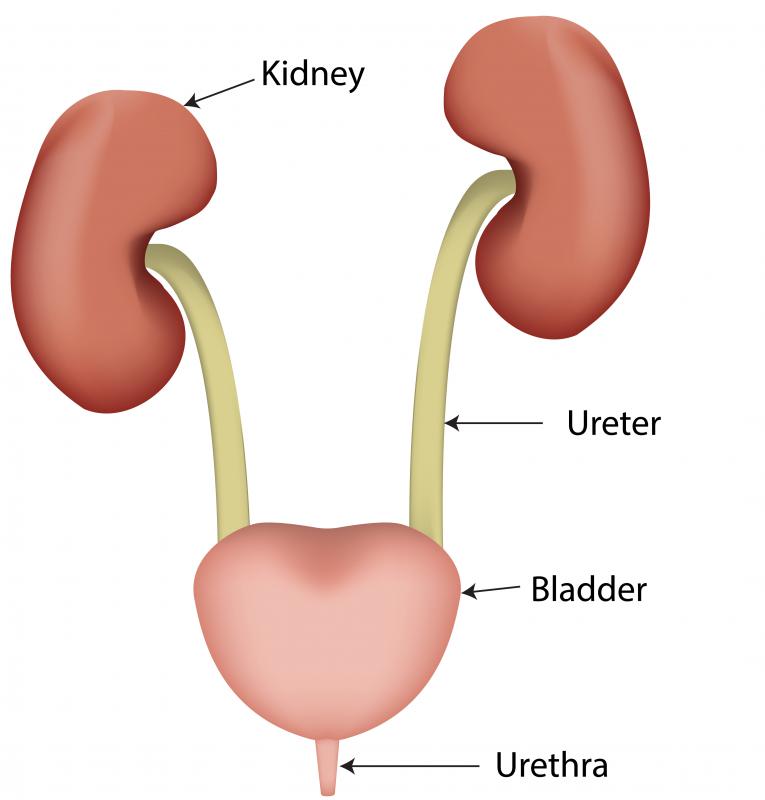

location of the bladder in the human body

Posts: location of the bladder in the human body